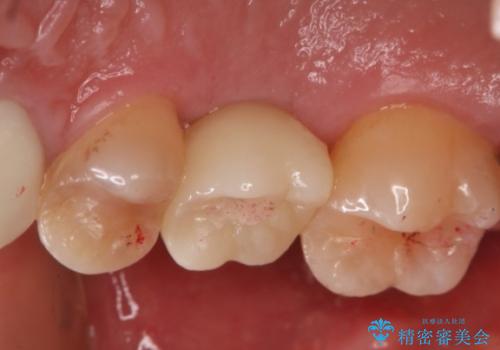

- 右上6番の歯の欠損部の治療を希望され来院された患者様です。

インプラント治療を希望されたので、インプラントとセラミッククラウンでの治療を計画しました。

歯の欠損部への治療には入れ歯・ブリッジ・インプラントという治療が選択されますが、インプラント治療は天然歯を削ることなく治療を行うことが出来ます。